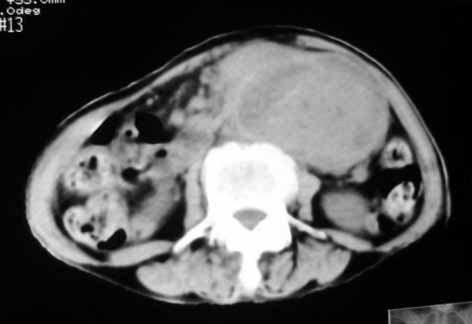

1.中腹部腹主动脉旁可见巨大包块影,其形态似为2个(或分叶),与腹主动脉分界不清,边界较清,其内密度不均匀(稍高、不匀称低密度),腹膜后未见确切肿大淋巴结...性质?考虑腹主动脉瘤可能性大,不排除平滑肌瘤及畸胎瘤可能,建议增强ct;

考虑:1、左侧腹膜后占位性病变(以间叶源性肿瘤可能性大);

腹膜后软组织肿块,密度不均匀,病灶分叶,降主动脉受浸犯

考虑:来源于腹膜后间叶组织的肿瘤

脂肪肉瘤,平滑肌肉瘤的可能性大。支持!(本例关键是定位,仔细分析,可以观察到主动脉被包埋于肿瘤内,因此可定位于—来源于腹膜后的实性肿瘤。)

腹膜后肿块侵犯腹主动脉及肠系膜上动脉,肿块密度不均,1来源间叶组织肿瘤,2肠系膜恶性肿瘤可能大,